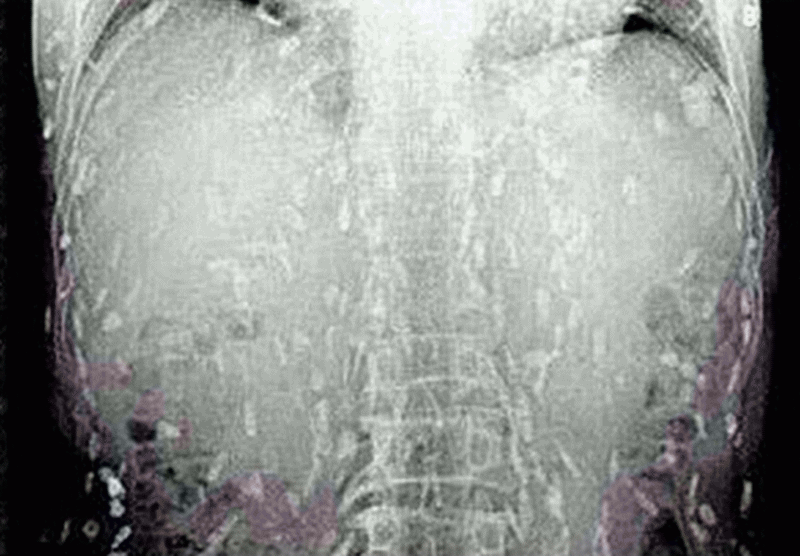

А все началось с того, что китаец пошел к доктору с жалобами на боли в животе и сыпь на коже, передает Day.Az со ссылкой на Soulpost.ru. К его ужасу, рентген показал, что все его тело заражено глистами - солитерами, ленточными червями.